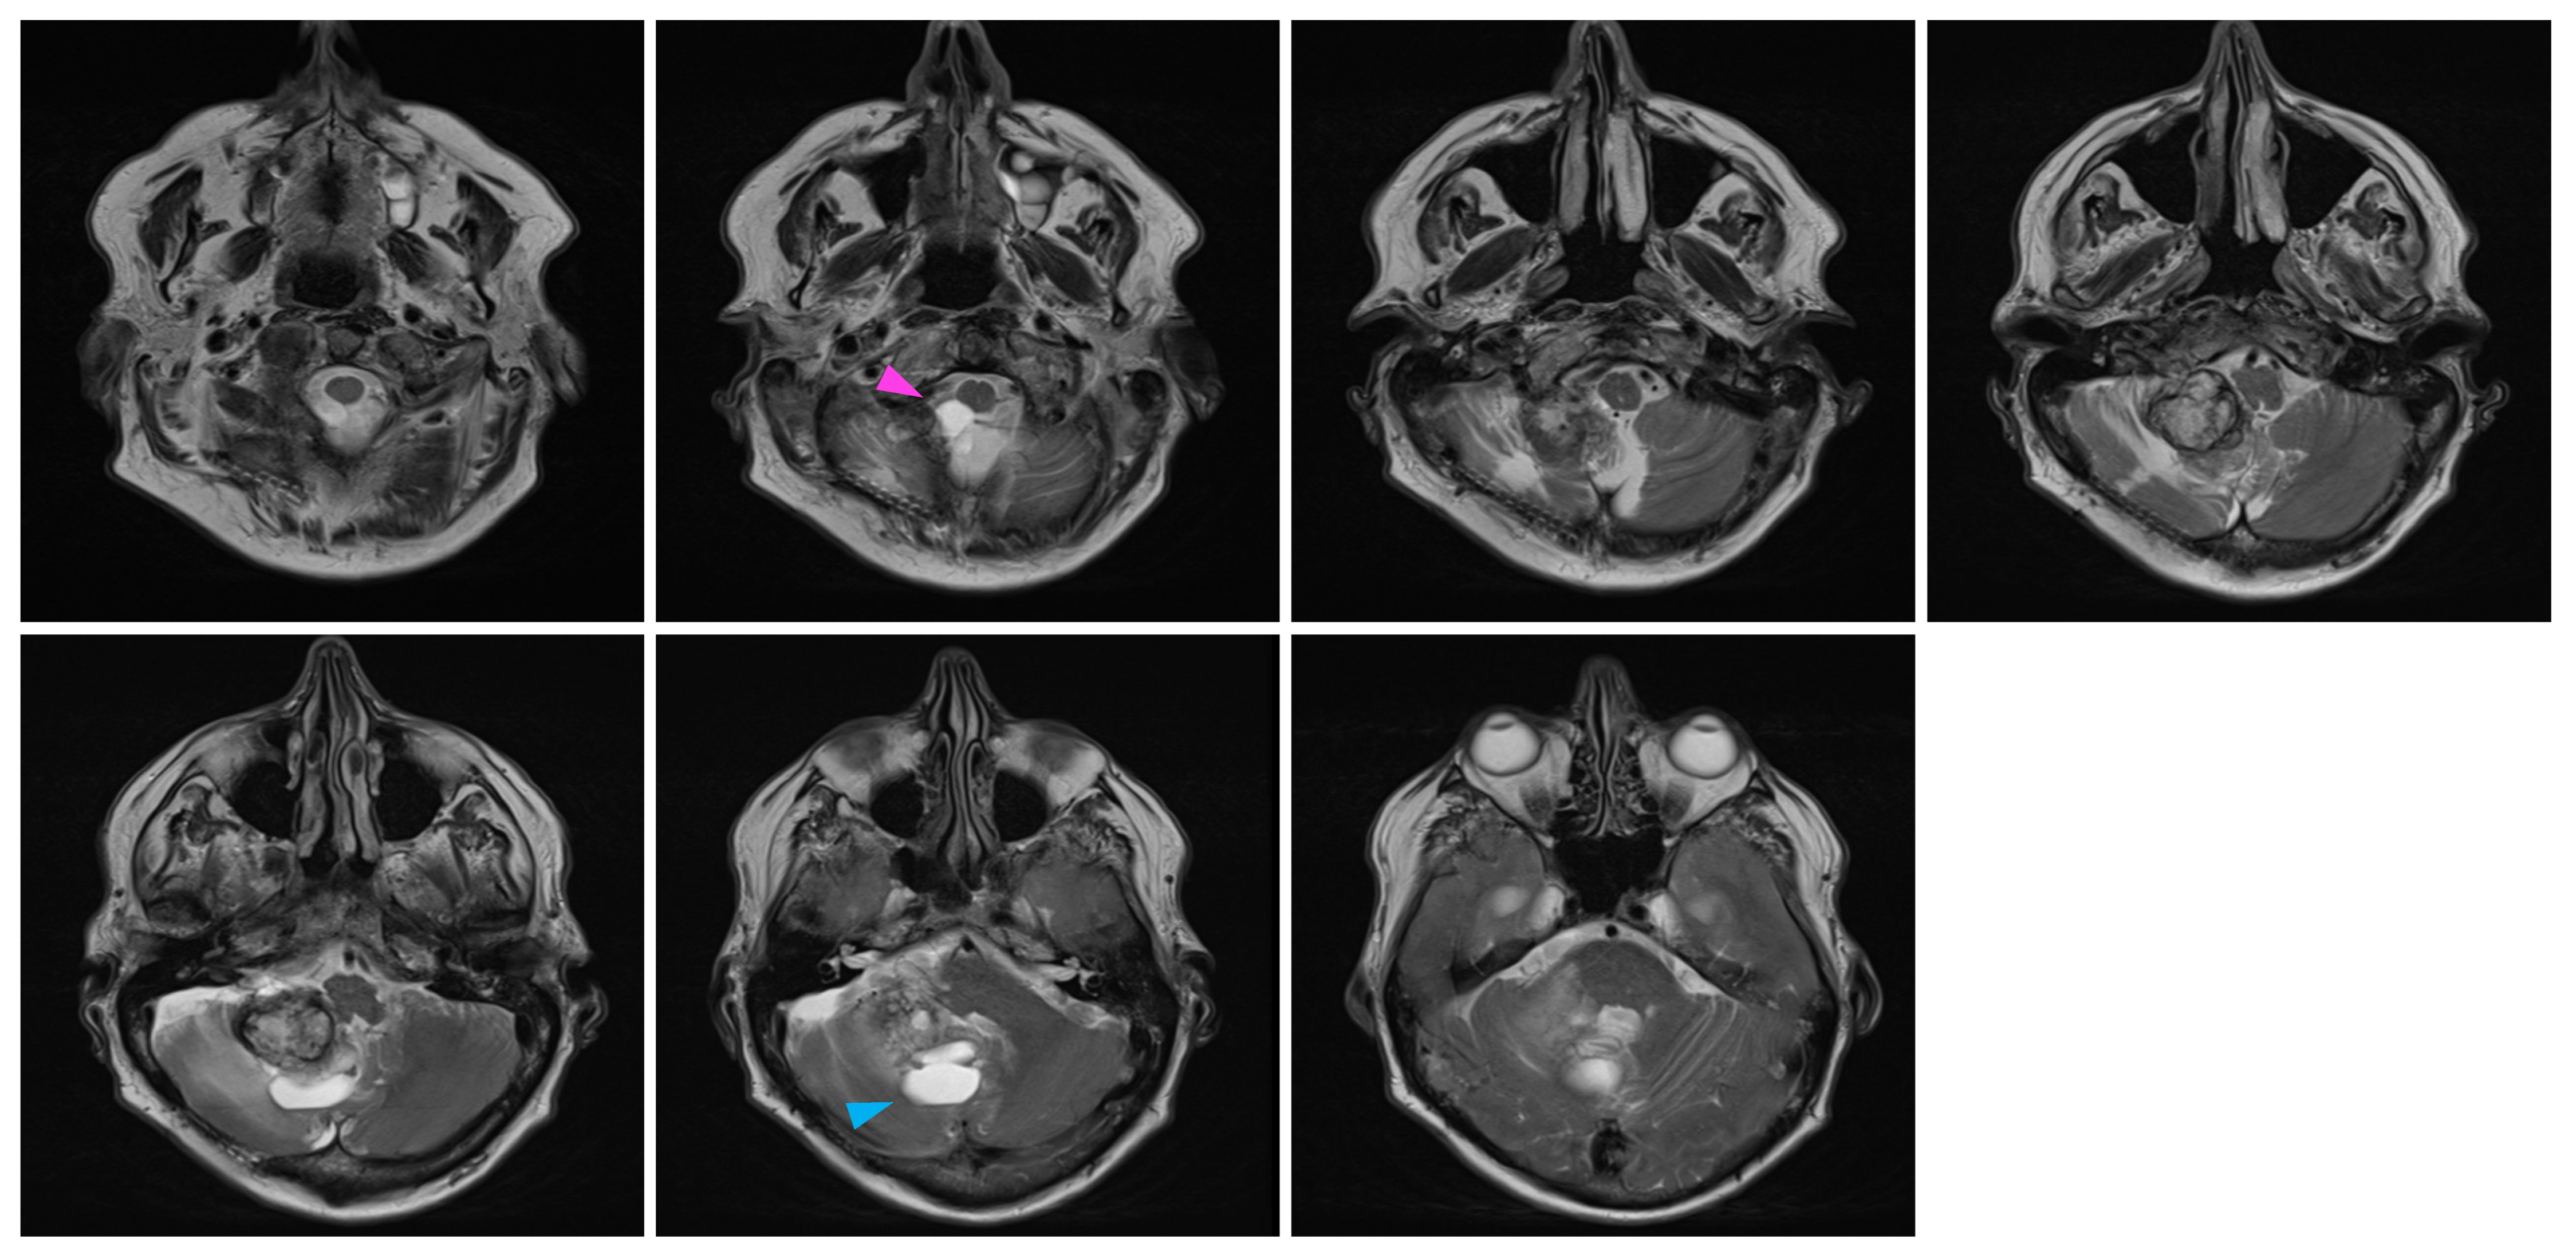

In February 2022, at the age of 72 years old, the patient was hospitalized in his hometown following the appearance of symptoms and was referred to neurosurgery. He mainly displayed loss of balance, unexplained loss of weight, confusion, and psychomotor retardation. He was able to ambulate without the aid of a walker, albeit at a very slow pace. Dexamethasone failed to improve his condition. An MRI underlined a right-sided, cerebellar intra-axial lesion located at the anterolateral portion of the cerebellar hemisphere. The lesion, determined to be a relapse of the initial HBL, displayed a nodular component in intimate proximity with the brainstem, measuring 36.2 × 32.1 × 31.9 mm (Figure 3). The presence of two cystic components were also noted. The first, located posteriorly, measured 32 mm maximally (Figure 4, blue marker). The second, located antero-infero-medially, measured 21 mm maximally and protruded in the subarachnoid space at the level of the pons (Figure 4, pink marker). The lesions caused a mass effect on the medulla, the inferior aspect of the pons, the middle cerebellar peduncle, and at the level of the 4th ventricle with associated hydrocephalus.

Figure 4.

Pre-surgical MRI of the lesion. Representative capture of the T2-weighted MRI pre-surgical imaging highlighting the two cystic components of the lesion. Coronal images are organized left to right and represent a posterior-to-anterior progression in the coronal plane. The pink marker highlights a 21 mm antero-infero-medial cystic lesion, while the blue marker highlights a 32 mm posterior cystic lesion.